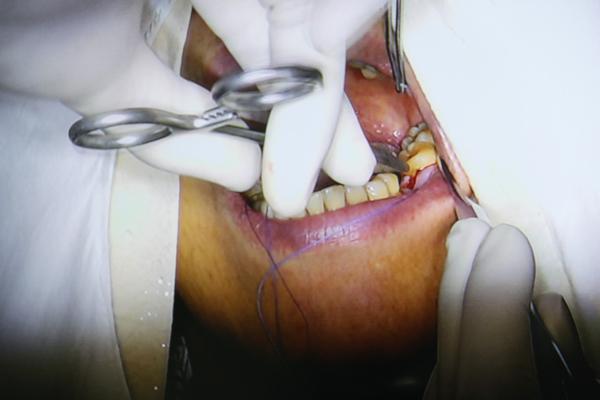

种好后对种植部位进行缝合

8分钟后,种植手术完成